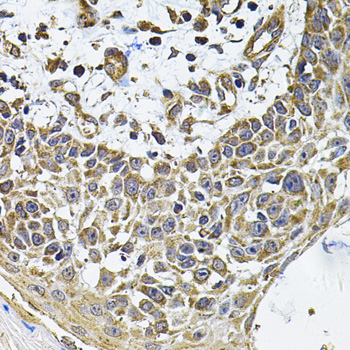

Immunohistochemistry of paraffin-embedded human skin carcinoma using ICOSL at dilution of 1:100 (40x lens).

Immunohistochemistry of paraffin-embedded human kidney using ICOSL at dilution of 1:100 (40x lens).